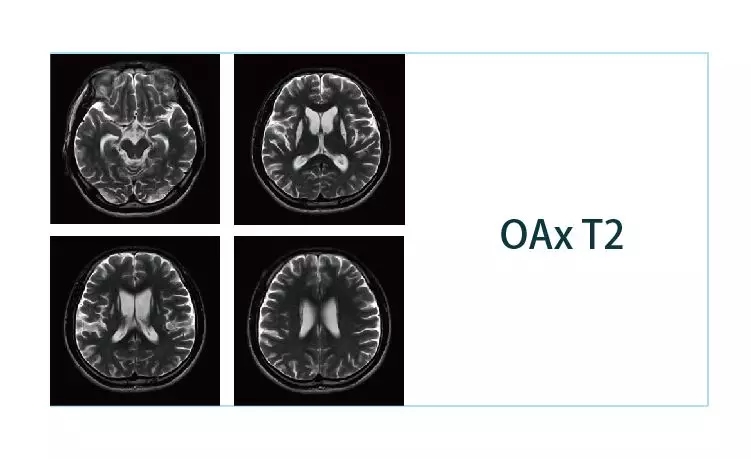

【朗润影像档案】20190111磁共振影像病例结果讨论